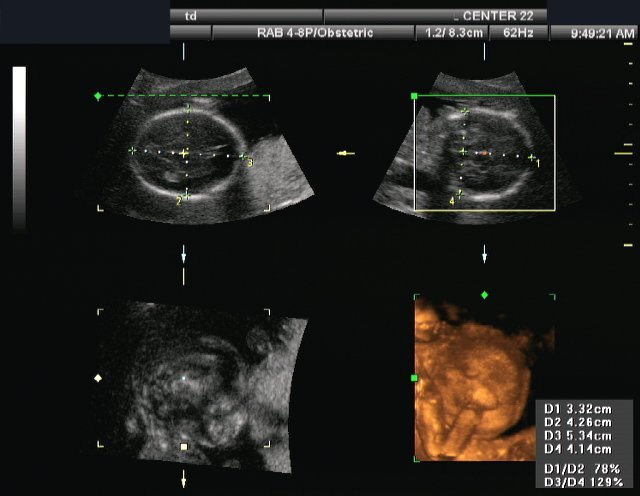

La razón por la que los precios de los ultrasonidos 3D y los ultrasonidos 4D no están cubiertos por el seguro es porque no son un procedimiento necesario. Los ultrasonidos 2d regulares son suficientes para que el médico tenga una idea de lo que está sucediendo. Sin embargo, muchas mujeres embarazadas están dispuestas a pagar el dinero extra porque obtienes mucho más de este tipo de ultrasonidos. En lugar de tener una imagen bidimensional plana, puede experimentar su primer vistazo de su hijo en una imagen tridimensional. Con estas imágenes mejoradas, podrá distinguir las características del Niño más fácilmente. También puede ver las expresiones faciales que se están realizando en el momento de la ecografía.

Como puede ver, los precios de los ultrasonidos 3D de los ultrasonidos 4D pueden ser muy asequibles si simplemente se toma el tiempo para encontrar las mejores ofertas. Al tomar este tiempo, puede estar seguro de aprovechar un servicio que le brindará mucha alegría y felicidad. Las fotografías que se lleve a casa serán memorables en los años venideros cuando se las muestre a sus amigos y familiares. Si no estaba considerando un ultrasonido 3D Ultrasonido 4D antes, ¡espero que lo esté ahora! Ver a su hijo en 3 dimensiones dentro del útero puede ser una experiencia mágica y usted atesorará los recuerdos durante toda su vida.